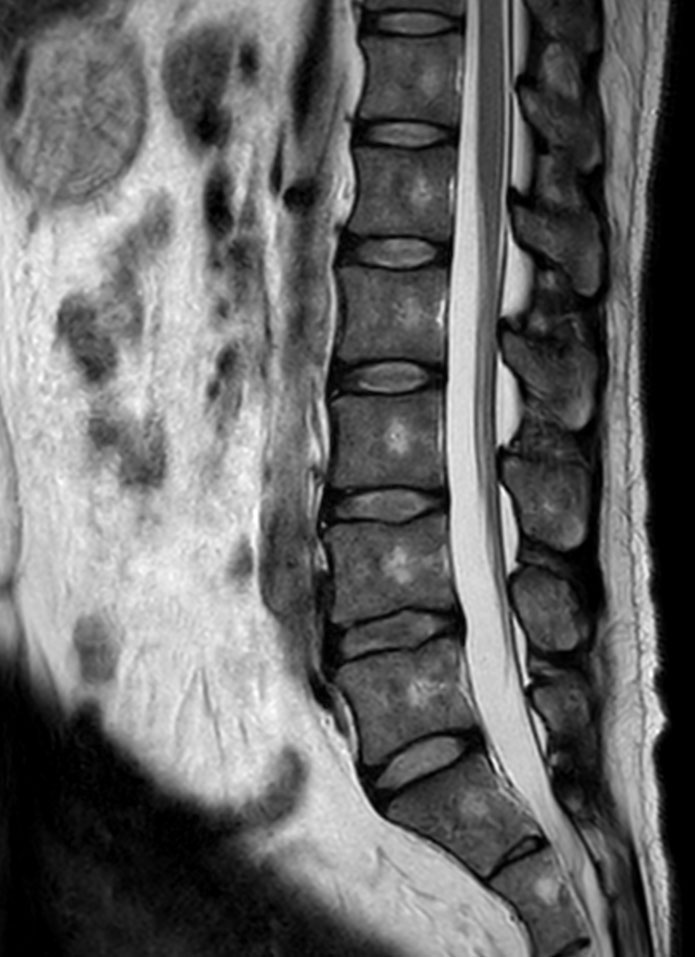

Neurography schwannoma (Compressed SENSE)

Patient with a lumbar neurography schwannoma.